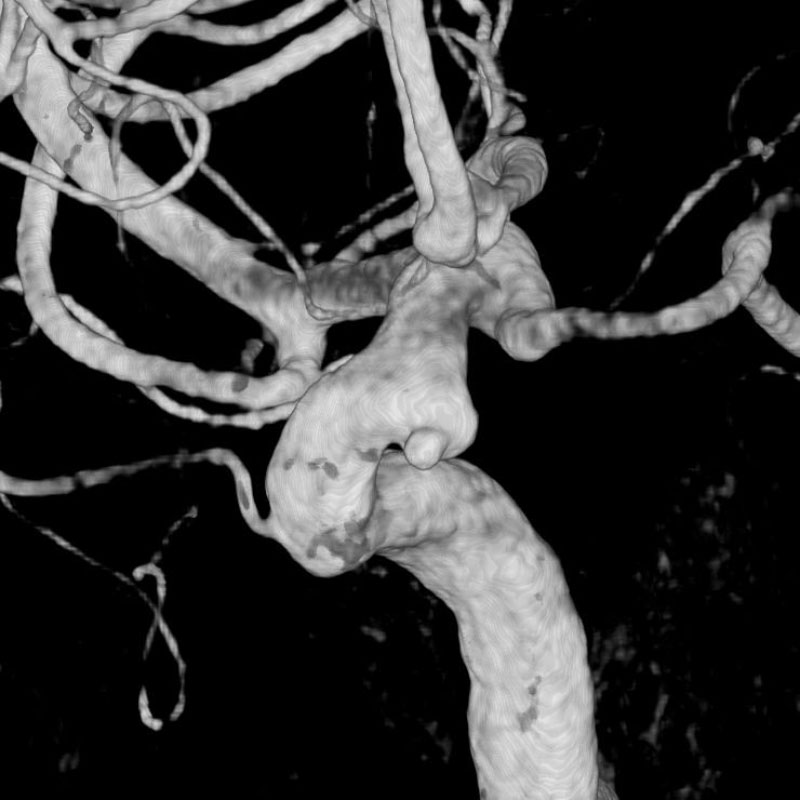

脳動脈瘤(Acom)

脳血管内手術

芝野/古谷/木本